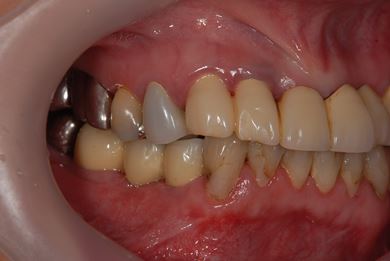

インプラントの症例写真 IMPLANT

骨再生インプラント治療

| カテゴリー | 【インプラント治療】【セラミック治療】 | ||||||||||||||||||||||||||||||||

| 性別/年齢 | 女性 / 40歳 | ||||||||||||||||||||||||||||||||

| 主訴 | 右下のブリッジが外れているかもしれないという診断を受けましたが、開けてみないとわからない、場合によっては部分入れ歯と言われ、セカンドオピニオンを希望。腫れがあるのも気になります。 | ||||||||||||||||||||||||||||||||

| 治療方針 | 右下奥、骨再生法によりインプラント治療を可能にする。 | ||||||||||||||||||||||||||||||||

| 治療内容 | インプラント3本(GBR、テンポラリーインプラント+仮歯)、ハイブリッドセラミックブリッジ3本、ハイブリッドセラミッククラウン2本 | ||||||||||||||||||||||||||||||||

| 総治療費 | 1,524,338円 | ||||||||||||||||||||||||||||||||

| 治療期間 | 1年0ヶ月 |